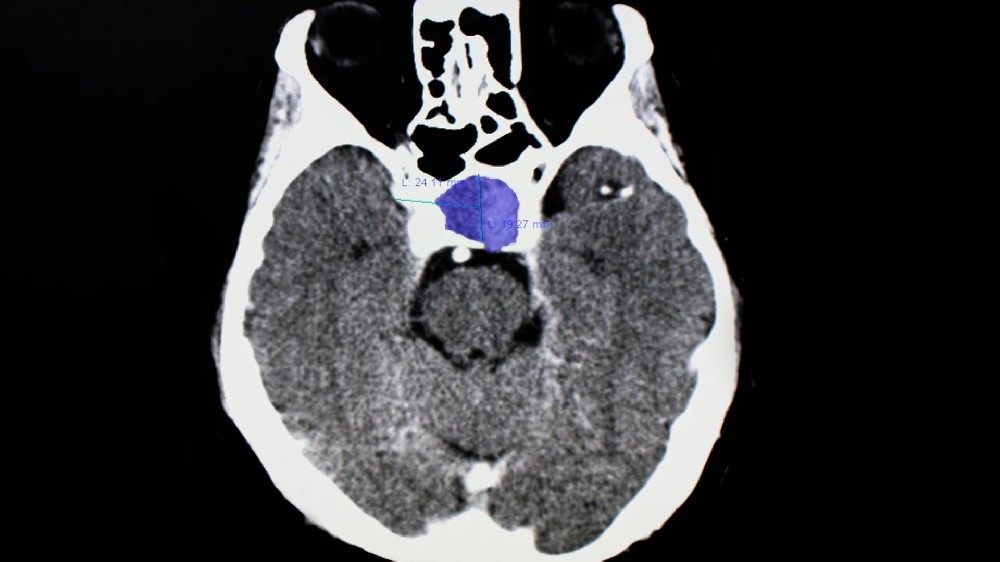

傳統的造影技術如**MRI(磁力共振掃描)**是檢測**垂體瘤(垂體腺瘤)**的基礎,因為它們在建立軟組織(如垂體)的詳細影像方面表現卓越。**MRI** 仍然是檢視垂體腺瘤、界定其大小以及評估其是否影響周圍結構的黃金標準。

此外,**PET-CT (Positron Emission Tomography-Computed Tomography) **也可能用於某些病例。這有助於顯示腫瘤的新陳代謝活動,提供額外的洞察力。這對於區分垂體腺瘤和其他腦部病變尤其有用。